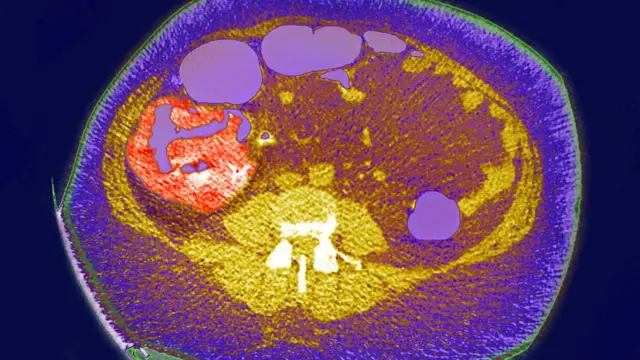

ছবির উৎস, BSIP